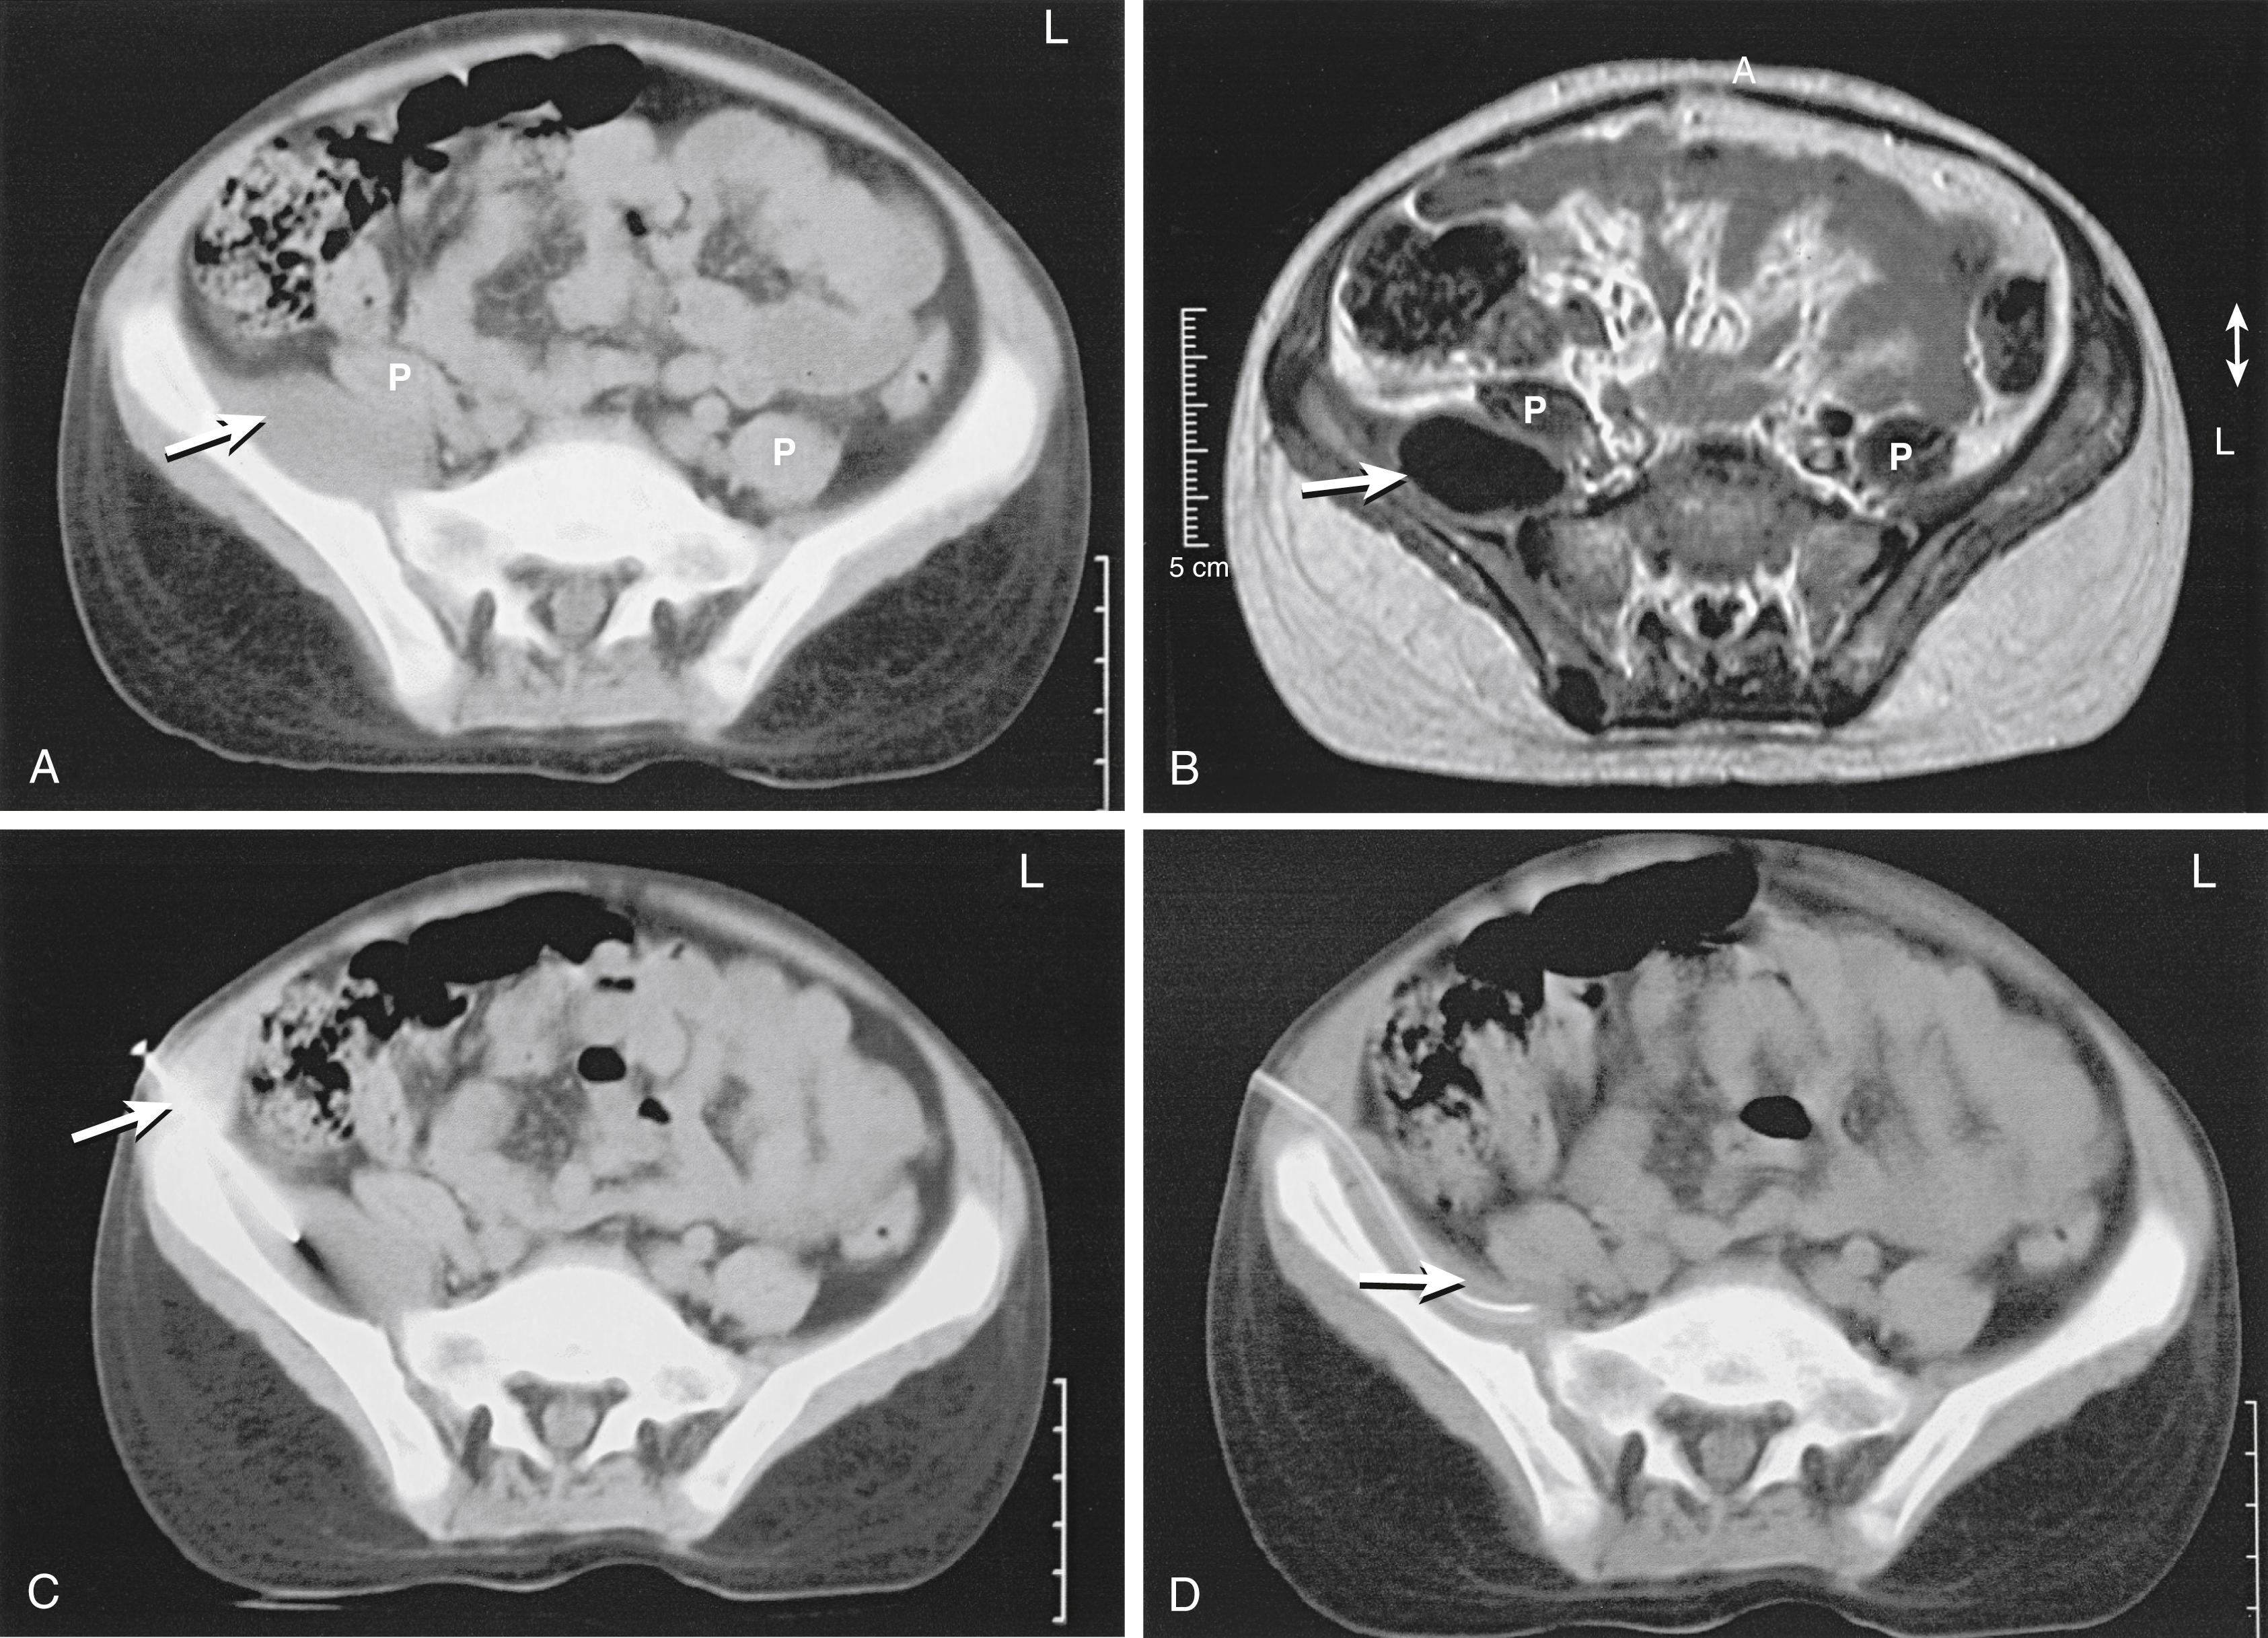

Although CT is excellent for defining the features of bone, this method has limited application in the diagnosis and management of osteoarticular infections because the bony changes associated with osteomyelitis are usually adequately visible on plain films. However, CT is useful in the delineation of bony sequestra and segmental defects in chronic osteomyelitis. It may also be helpful in demonstrating deep infections of the spine or pelvis. CT may be used for guided percutaneous biopsy of the spine or for the placement of drains in pelvic abscesses along the inner wall of the ilium ( Fig. 23.8 ).

FIG. 23.8, Computed tomography (CT) scan (A) and magnetic resonance image (B) demonstrating a psoas abscess (arrows) displacing the right psoas muscle (P) . CT-guided percutaneous drainage (C) was performed, with placement of a drainage tube (D).